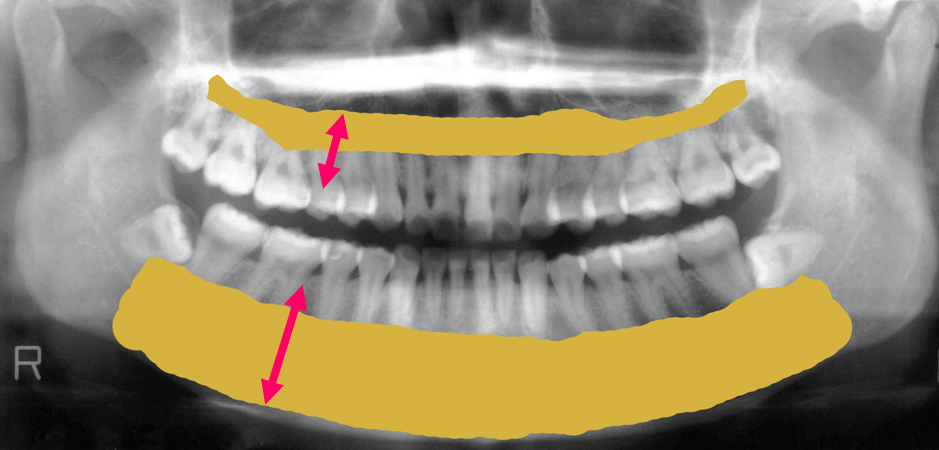

下顎の骨の部分に黄色い線を引いている部分があります。ここにはうっすらとですが白い線が確認できます。

これは下顎管といい大きな神経と血管が通っている管です。

この管はとても重要なものなんです。

インプラント手術や大きな外科手術を行う時にはこの下顎管に傷をつけないようにしなくてはいけません。

下顎管は神経血管を通じて歯に栄養や血液を送っているとても重要なものです。

私たちの歯や歯茎が痛いと感じるのもこの重要な神経がきちんと機能しているからなのです。